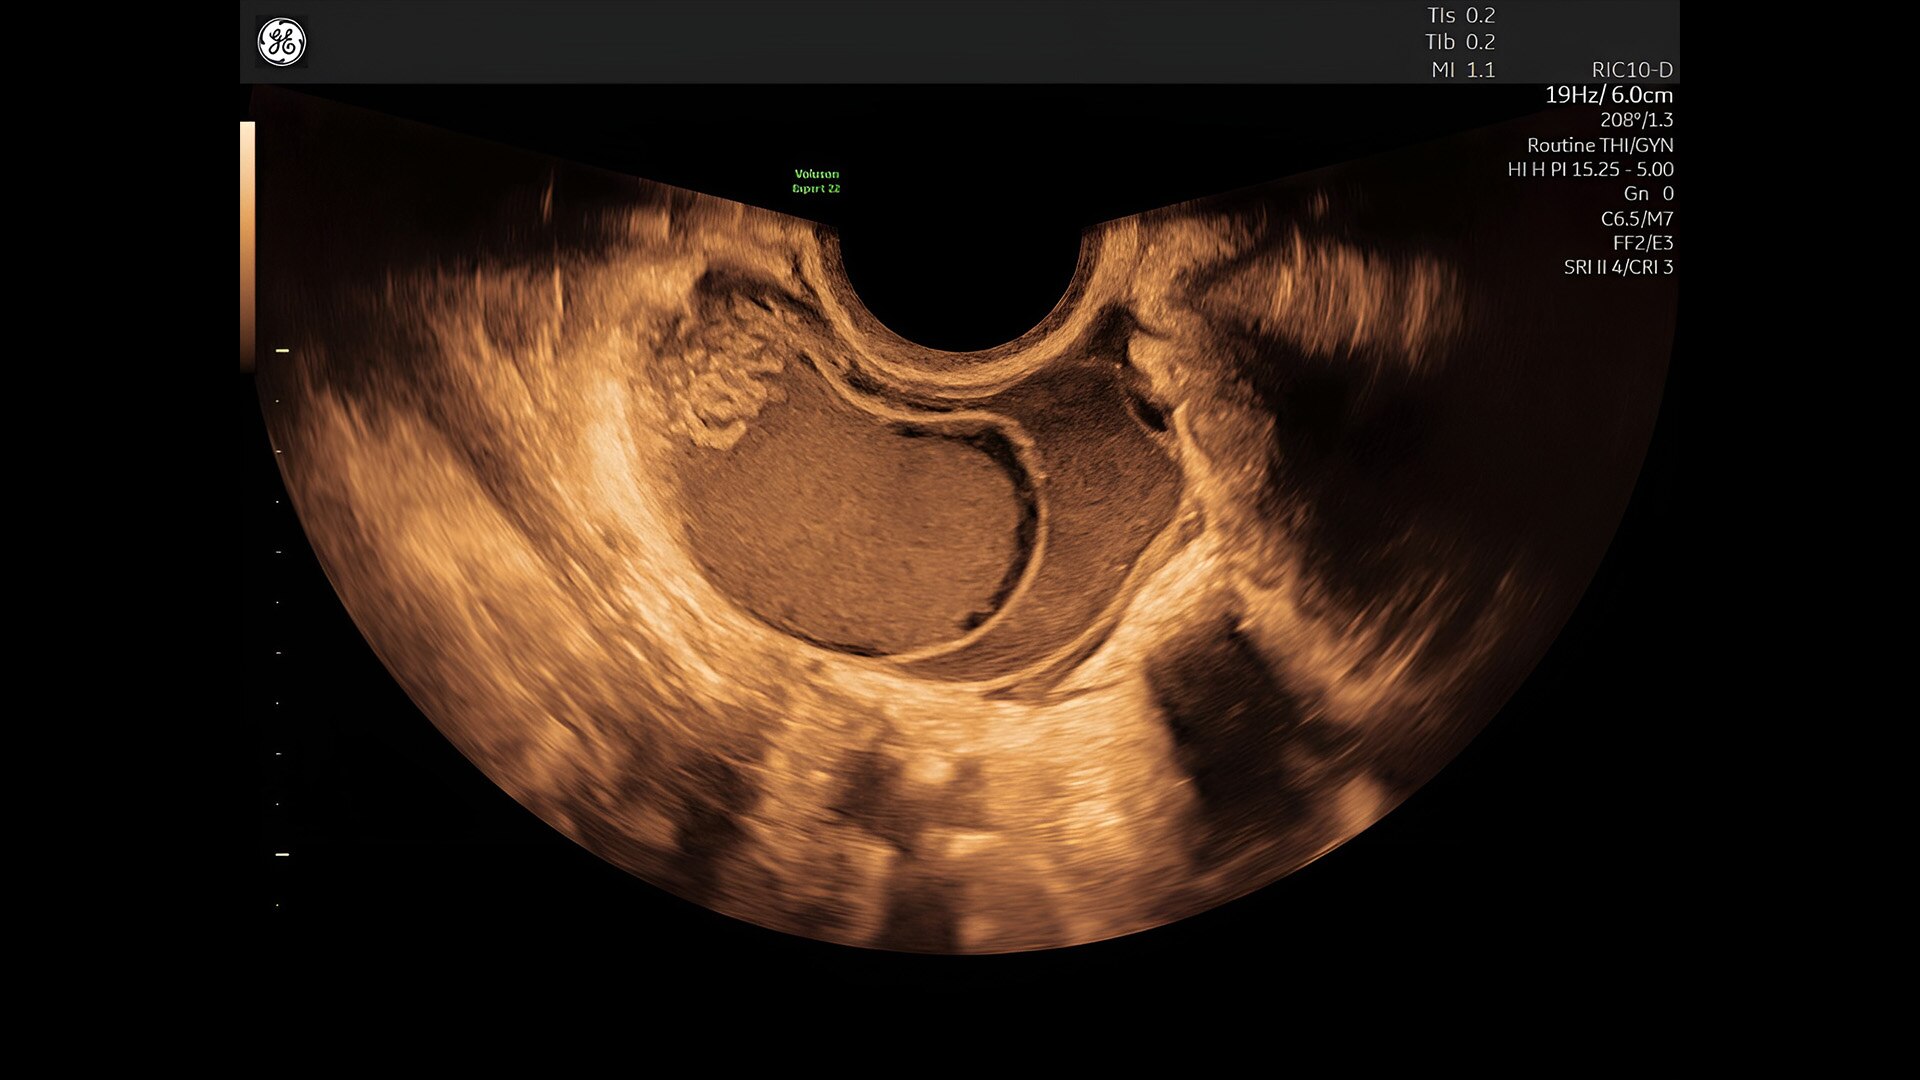

Pelvic health

Offer patient answers faster with Ai-based automation tools